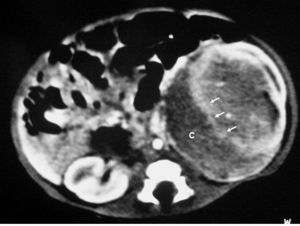

Los pacientes con diagnóstico histológico de tumor quístico multilocular (n = 7) tenían entre 5 meses y 12 años, siendo 4 de ellos varones y 3 mujeres. La clínica inicial fue la de masa abdominal palpable en 5, hematuria en uno y dolor abdominal en el paciente mayor. Se identificaron masas renales bien definidas que presentaban un aspecto quístico, con múltiples loculaciones separadas por septos que mostraban discreto realce (figs. 3 y 4). En un paciente se encontraron focos de blastema en las paredes de los septos en el estudio histológico.

Fig. 3. Tumor quístico multilocular. (A) Ecografía abdominal. Corte renal longitudinal. Masa renal heterogénea con predominio de áreas anecoicas. (B) Tomografía computarizada abdominal con contraste intravenoso. Corte sobre polo superior renal izquierdo. Masa de aspecto multiquístico que presenta zonas de parénquima renal sano entre las formaciones quísticas.

Todos los pacientes quedaron libres de enfermedad tras la nefrectomía. En un caso pudo hacerse cirugía conservadora (tumorectomía) por tratarse de una masa de pequeño tamaño (fig. 4).

Fig. 4 Tumor quístico multilocular. (A) Ecografía abdominal. Corte renal longitudinal. Masa en tercio medio de riñón derecho, multiquística. (B) Tomografía computarizada abdominal con contraste intravenoso. Corte al nivel de los hilios renales. Cavidades hipodensas, tabicadas. (C) Resonancia magnética T2 coronal. Cavidades hiperintensas separadas por septos hipointensos bien definidos.

Los estudios radiológicos muestran una masa de gran tamaño, encapsulada, con múltiples quistes no comunicantes, que pueden herniarse hacia la pelvis y el uréter y cuyos septos presentan un realce irregular bajo o moderado4,8,9.